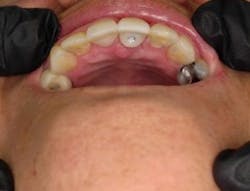

Tefball serves the same purpose as materials like cotton pellets, PVS, and Teflon tape, acting as an interface between the screw hole of a dental implant and the composite filling cover. The superiority of this product lies in its antimicrobial properties as well as its unique physical design, material composition, and durability (figure 2).

Tefball is perfectly sized to fit implant access holes, featuring a distinctive design crafted to prevent composite infiltration while ensuring optimal engagement for effective retention (figure 3). It is explicitly calibrated to match the diameter of the access cavity, providing a seamless and efficient solution for your dental implant needs (figure 4). Using Tefball saves time and money and ensures a better outcome for patients. The product stands out for its cleanliness, antimicrobial properties, hygiene, and ease of insertion and removal.